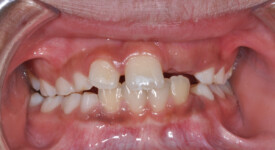

This is an example of a teenage patient with photographs of their smile before and after treatment at Braceline. Our orthodontic treatments are designed to provide maximum results in minimal time and to help you achieve the smile you always wanted!

Before Transformation!